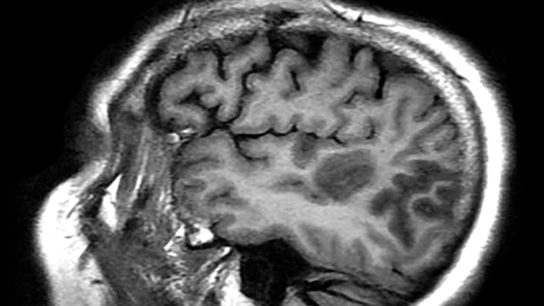

Because of the relative rarity of stroke in children, many clinicians tend to presume that mimics are the cause of the symptoms.

The new guidelines include a step-by-step diagnostic algorithm for use in the clinical setting, as well as a special emphasis on neurobehavioral impairment.

It’s important for pediatric neurologists to spend time preparing the patient for the transition to adult care.